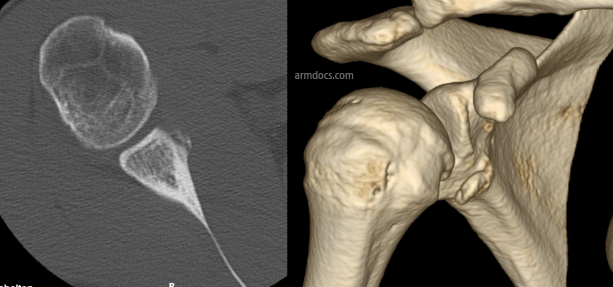

The procedure is performed under a combination of general and regional anaesthesia. The skin on the front of the joint is incised and the subscapularis tendon is split. The inside of the joint is examined. The rim of the socket is freshened to promote bleeding and facilitate healing. A bone block is prepared using the coracoid process (a part of the shoulder blade) or bone taken from the pelvis and repaired to the defect in the socket using 2 screws and occasionally a mini-plate (these procedures are referred to as the Latarjet or Eden-Hybinette procedures respectively). In selected patients the bone block may be positioned and fixed arthroscopically using a pair of suture-button devices. The labrum and capsule is fixed back to the rim of the socket with suture anchors (small devices with sutures that are embedded in bone).

An appointment will be arranged for you at 2-4 weeks after the procedure. Follow-up is required for at least 12 months after surgery or until a satisfactory recovery is achieved. This will include X-rays at interval to check bone healing.